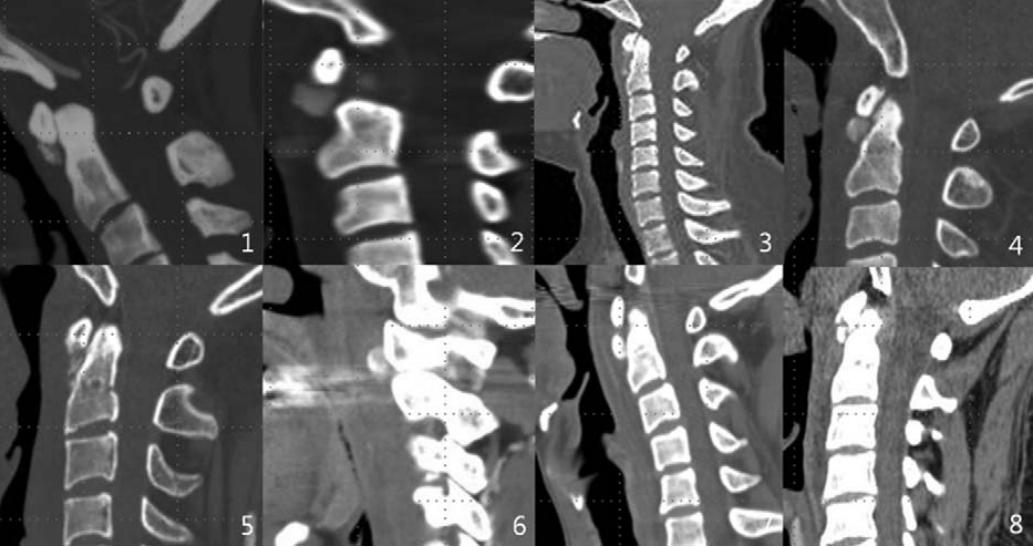

明确诊断主要通过影像学方法,颈椎CT是关键。 颈长肌钙化性肌腱炎特异性的影像表现是C1-4椎体前缘软组织肿胀和积液与C1椎体前弓下方不规则钙化沉着共存。

图:C1椎体前弓下方不规则钙化沉着

图:椎前积液

图:椎前积液和C1椎体前弓下方不规则钙化沉着

图:椎前软组织肿胀

CT的高分辨率能够明确肌腱内的钙化,能够明确是钙化而不是其他骨骼来源的高密度影。 钙化一般位于寰椎前弓的下方和枢椎齿状突的前方,少部分可位于下颈椎前侧 。CT有助于明确椎体前积液的存在和排除其他病理表现,如骨折或脓肿。MRI对诊断不是必须,但有时可帮助确定软组织异常,排除咽后脓肿,脊椎炎或肿瘤。 MRI检查T2加权在椎前可见局限性的裂隙样区域,大多位于C1-4水平,呈高信号改变,这反应是由于炎症引起的积液 。T2加权、脂肪抑制序列和T1加权对鉴别积液和脂肪组织、含脂肪的骨髓以及咽后感染、脊椎炎有重要作用。MRI检查在钙化检查方面存在不足,T2加权呈低信号。